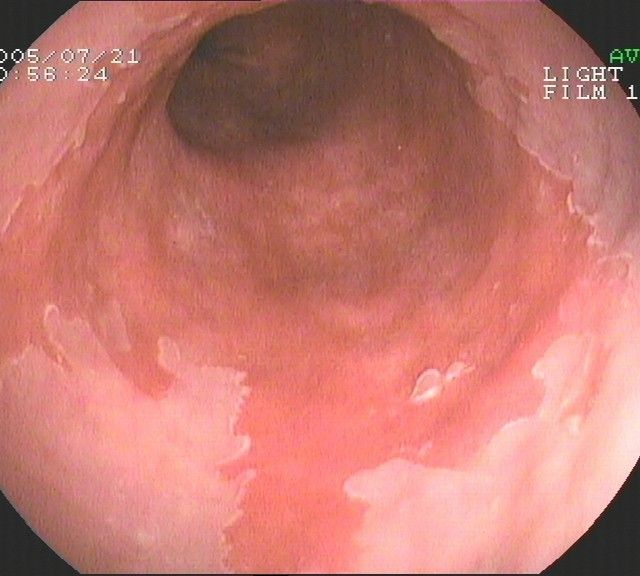

Coloskopie - Morbus Crohn, Befall der Dünndarmklappe